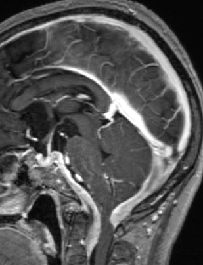

2013-8-2 MRI

2013-8-2 CT

腰穿脑压240